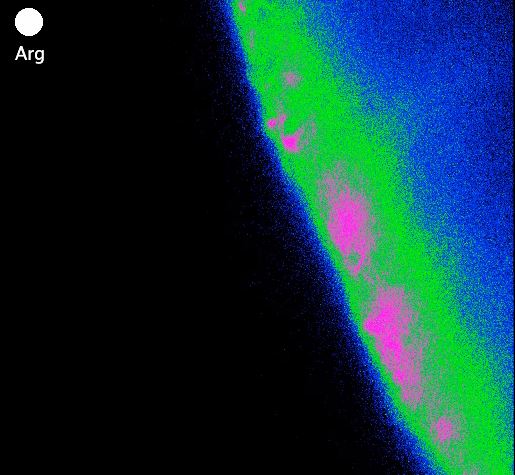

The researchers made their discovery by adding concentrated amounts of arginine and lysine into brain cells, which were made fluorescent so that any microscopic reactions would be visible. They observed that within thirty seconds, the tanycytes detected and responded to the amino acids, releasing information to the part of the brain that controls appetite and body weight.

Image 1: Tanycyte cells reacting to a puff of the amino acid arginine, credit Professor Nicholas Dale/Ms Greta Lazutkaite (click for short video clip)